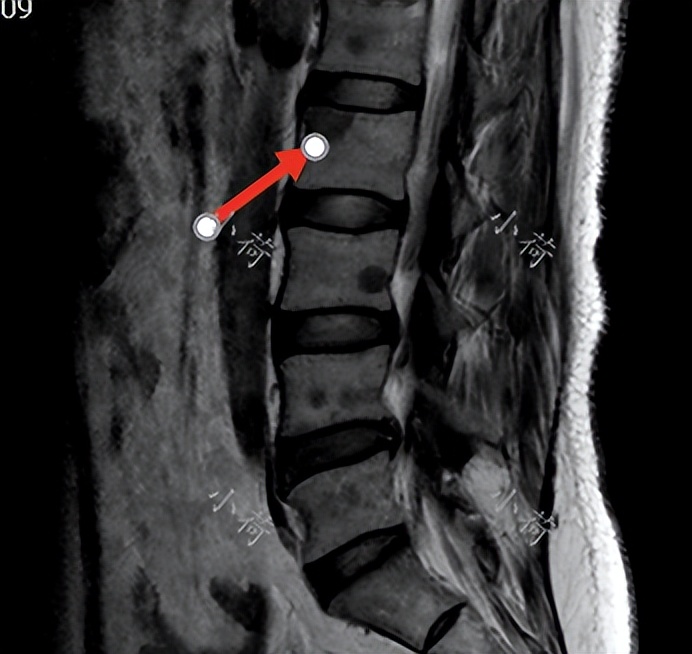

2018年,我第一次看到刘女士,是一位充满知性的女性,她确诊乳腺癌已经三年了,2015年发现左乳腺一个小小的肿物,就在我院乳腺外科完成了左乳腺保乳术加前哨淋巴结活检术,术后病理确诊为乳腺癌,进行了常规的化疗、放疗和内分泌治疗,不幸的是2018年夏天患者出现腰疼,检查提示发生了骨转移(图1),现在为了进一步治疗来到我的诊室。患者既往身体健康,已婚育有1女,无乳腺癌家族史。入院时的诊断:左侧乳腺癌,骨转移。

图1 腰椎MRI显示椎体转移